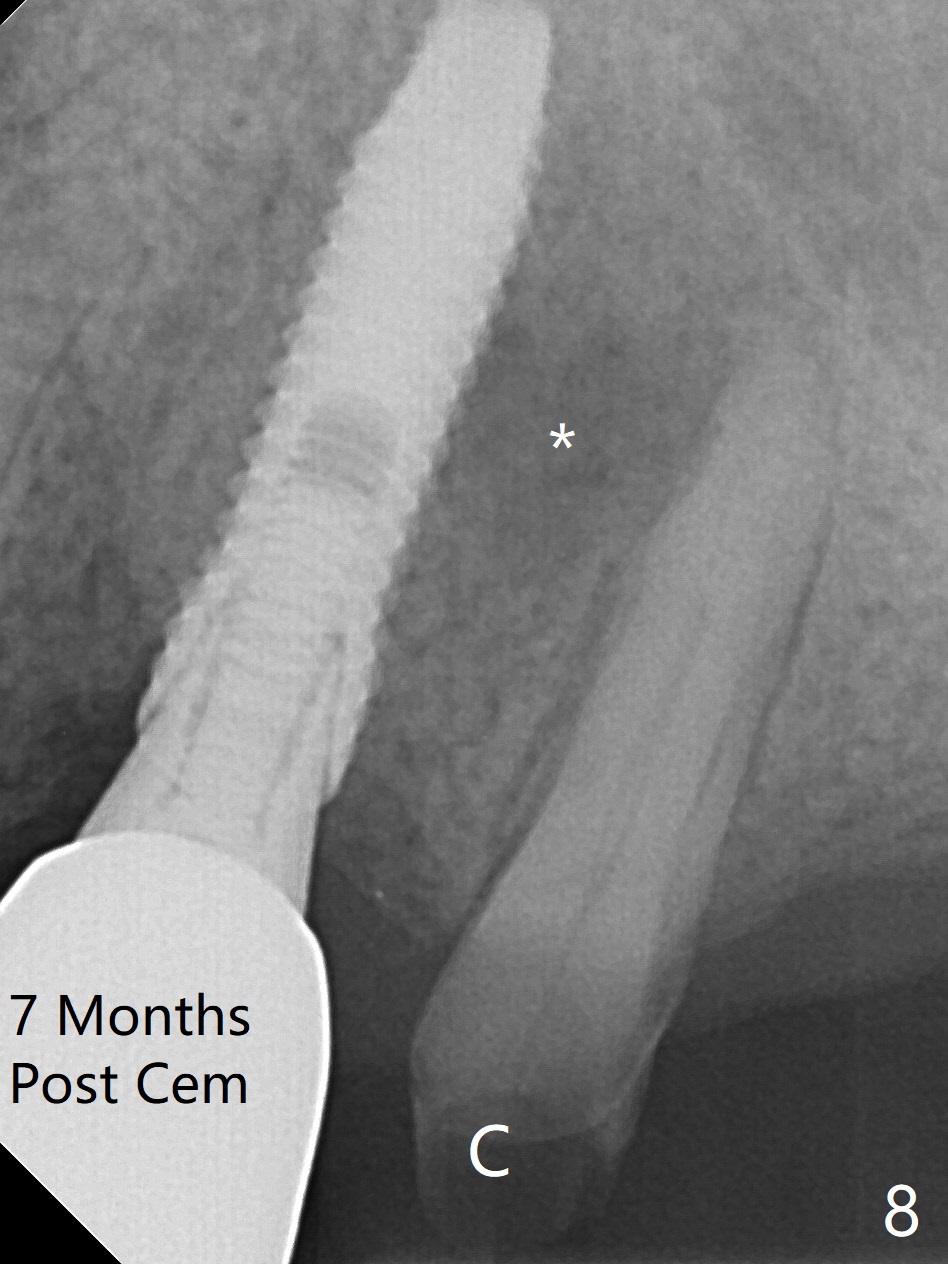

RPD Clearance